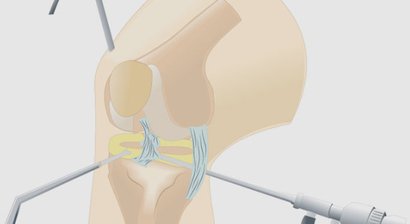

Im Falle einer notwendigen Operation wird diese von mir im Evangelischen Krankenhaus Wien durchgeführt. Meine chirurgischen Schwerpunkte liegen im künstlichen Gelenkersatz , in der Fußchirurgie und den arthroskopischen Operationstechniken.

Arthroskopie